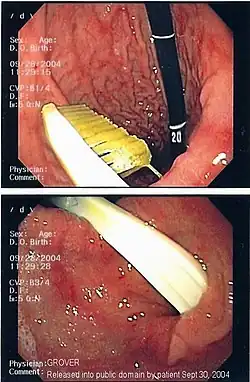

Knochensplitter oder Fischgräten können nach dem Verschlucken in die Schleimhaut des Schlunds oder der Speiseröhre eingespießt werden und dort zu Entzündungen führen. Verschluckte Fremdkörper, die in den Magen gelangt sind, gehen je nach Größe meist auf natürlichem Wege wieder ab. Bezoare (Trichobezoare, etwa eigene Haargeschwülste beim Menschen, und bei Tieren aus Pflanzenfasern gebildete Phytobezoare) können als Fremdkörper die Magen-Darm-Passage behindern.[1] Bei Knopfzellen wird die Entfernung aus dem Magen empfohlen, da eine Zerstörung der Hülle durch die Magensäure und ein Freiwerden giftigen Inhalts befürchtet werden muss. Grundsätzlich ist eine Entfernung bis in den oberen Dünndarm mittels Endoskopie möglich.